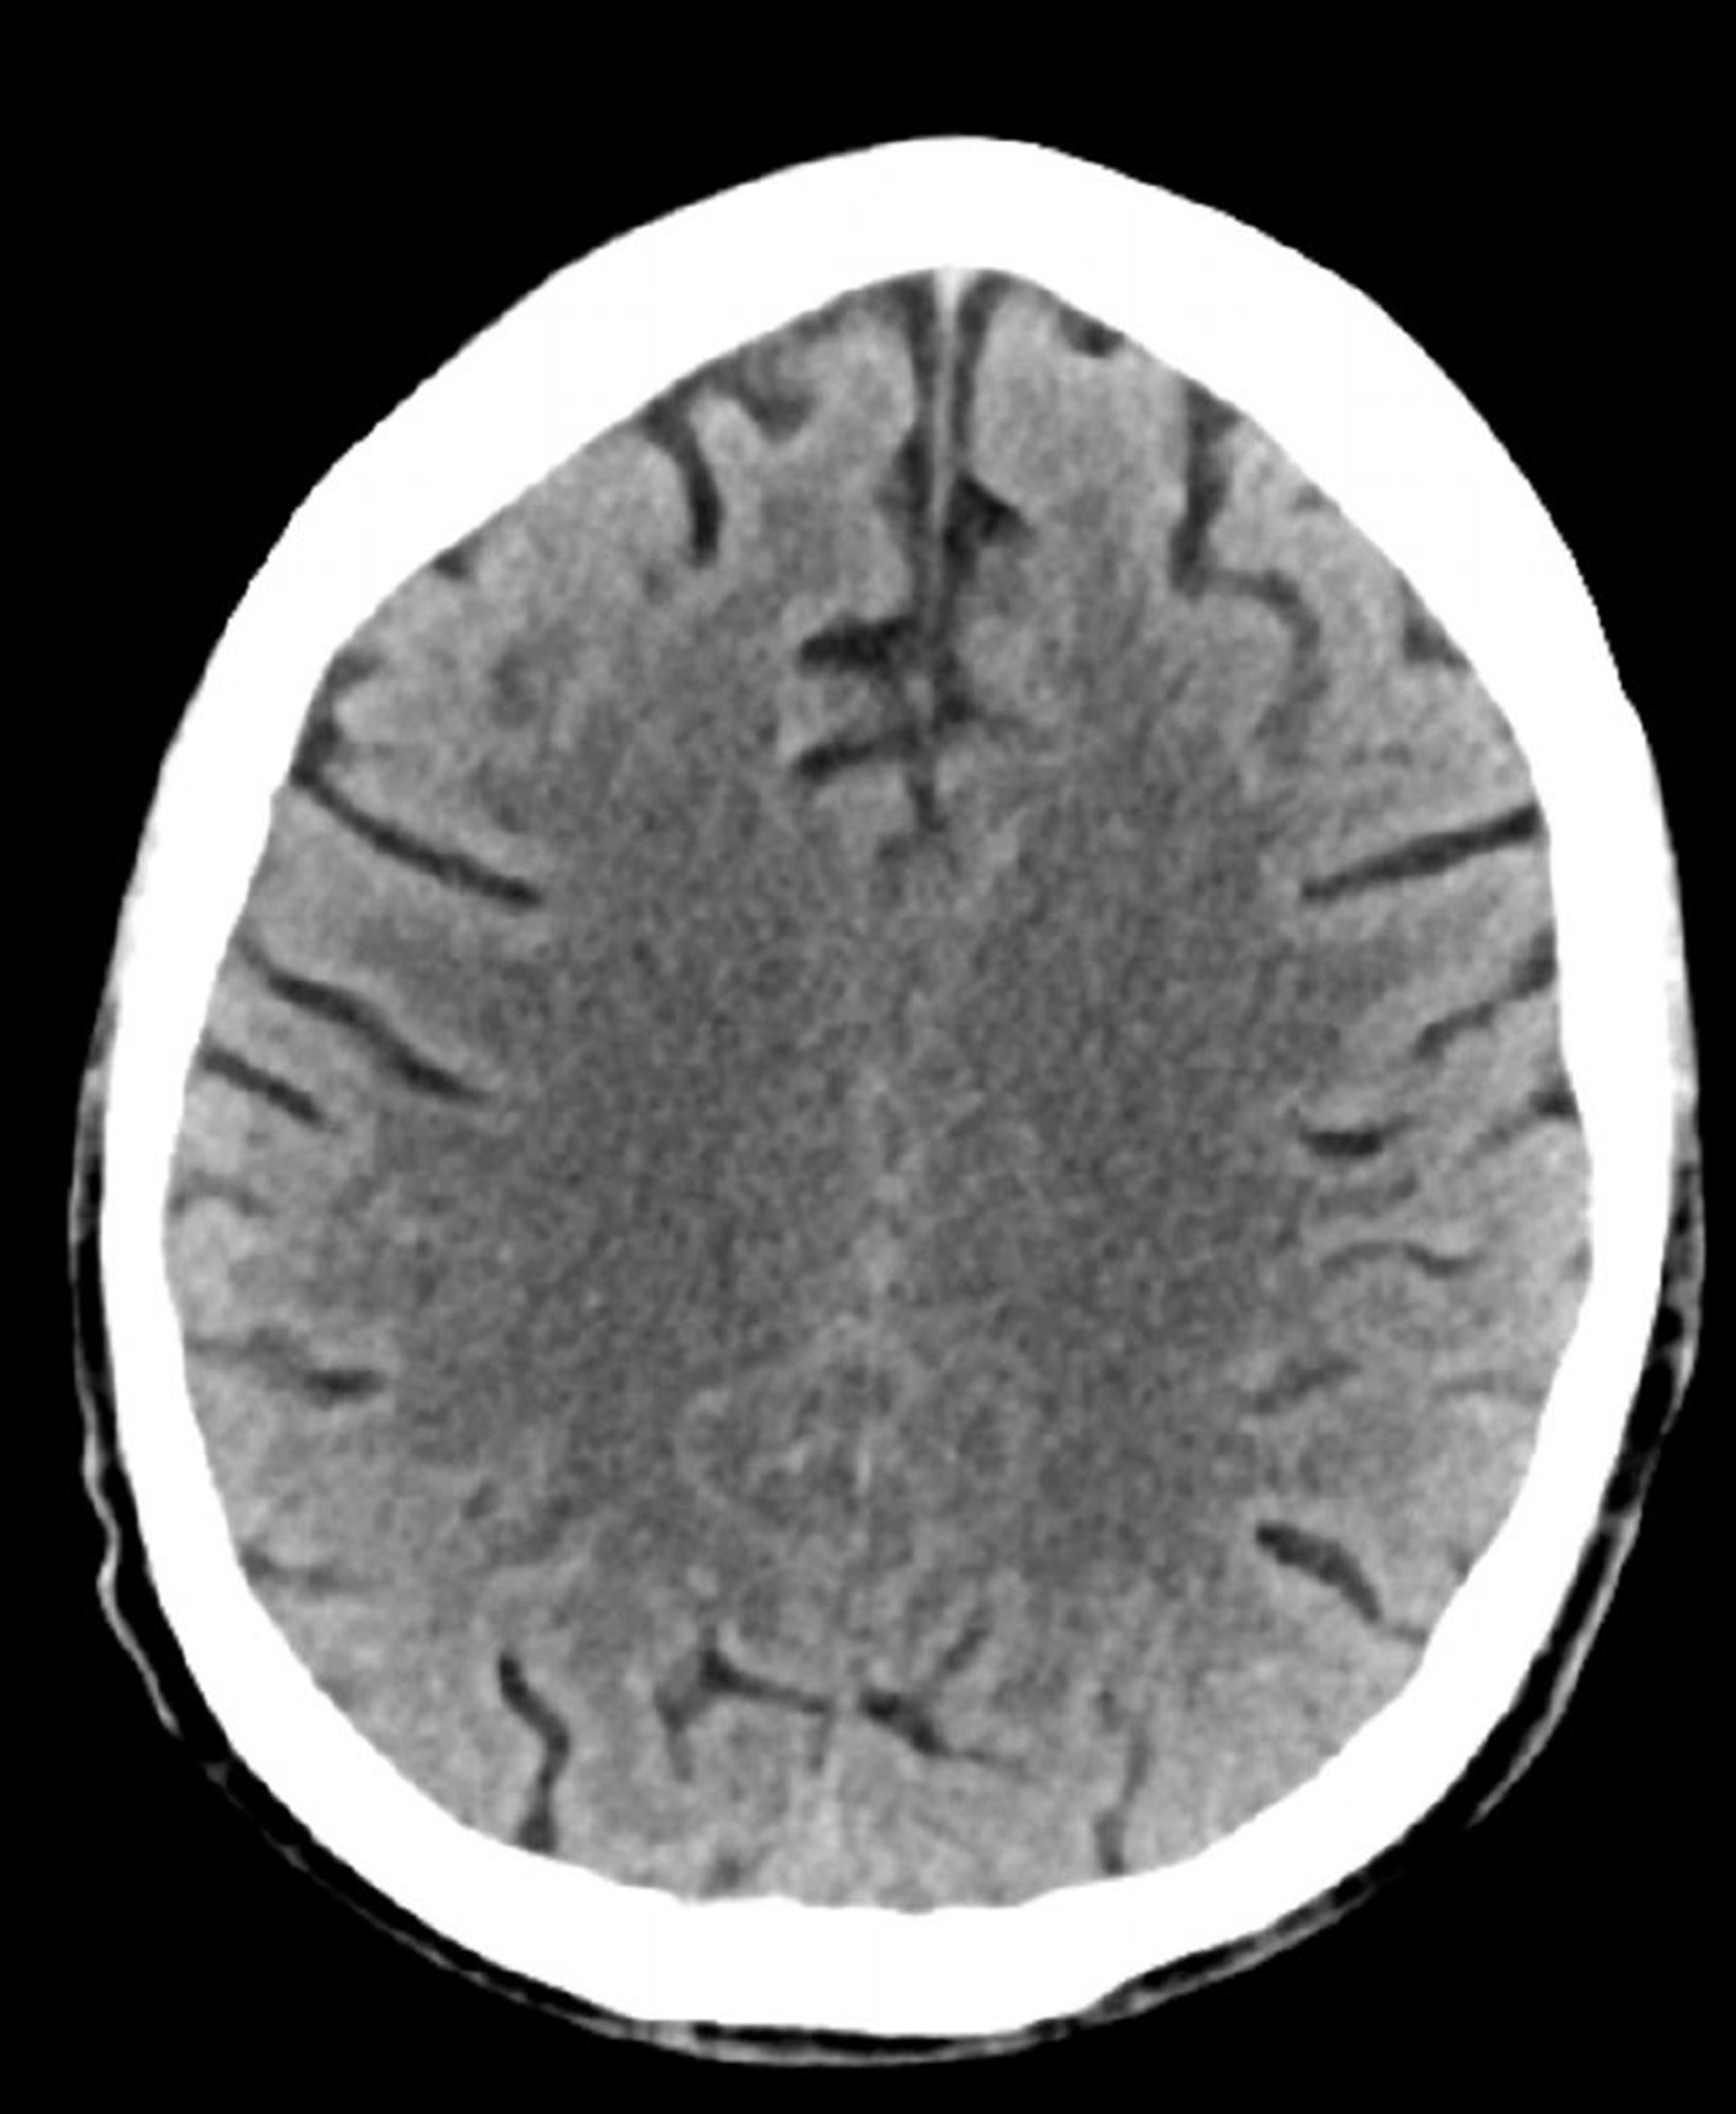

Стандартное КТ-сканирование головы (взрослые, возраст 74 года) – слайд 2

Это изображение –обычная компьютерная томография головы взрослого человека в возрасте 74 лет. По сравнению с нормальными результатами компьютерной томографии головы пациента 30-летнего возраста, мозговые борозды увеличены. Эти показатели являются нормальными для данной возрастной группы.